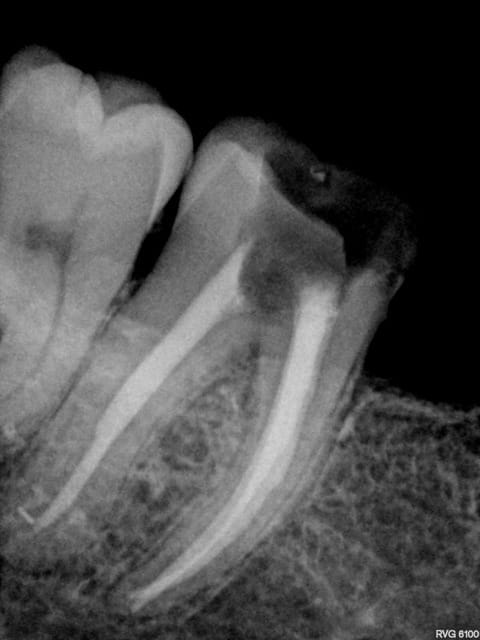

J'ai un de mes patients du cabinet où je travaillais avant qui m'a contacté car il a une reprise d'infection sous la CCM sur 46. Le praticien lui a déposé la couronne et va entreprendre le retraitement endodontique. Puis réaliser une nouvelle couronne. Etant donné que cela fait 3 ans que la couronne est posée le patient est mécontent. Il m'a appelé pour savoir s'il était possible d'avoir une indemnisation.

Je vous mets les photos en pièce jointe.

Ne leur dis surtout pas que tu as fait une faute. A la radio, ton obt est bonne.C'est tout.

Ton endo était pas mal.

C'est étonnant que le matériau d'obturation qui était dense en 2011 se soit dégradé à ce point et si vite.

Il est possible qu'il y ait autre chose (perfo latérale un peu en dessous du plancher, fracture de la racine MV).

Pour moi jusqu'à preuve du contraire c'est un alea.

Tu veux dire que, sur la radio, c'est à peu près blanc jusqu'au bout de la racine?

Parce que c'est tout ce qu'on peut dire sur cette endo. :-)))

Completement d'accord avec enlaye pour le multifactoriel ;l'infection est inter radiculaire , suite a une recession parodontale importante ,il suffit de voir la radio. Le retraitement (avec ou sans digue, :-)) est bien, mais ne donnera rien de plus!

Pour l'endo, c'est vrai que la disparition du matériaux d'obturation ne plaide pas en la faveur de notre jeune confrère.

La radio post-op du 15/11/2011 semble montrer la présence de cône de gutta dépassant coronairement . L'erreur ne viendrait-elle pas d'une empreinte de l'ic dans la foulée .

la préparation a retiré les cônes laissant le ciment endodontique.

Concernant une lésion interradiculaire je suis dubitatif en voyant uniquement cette radio .